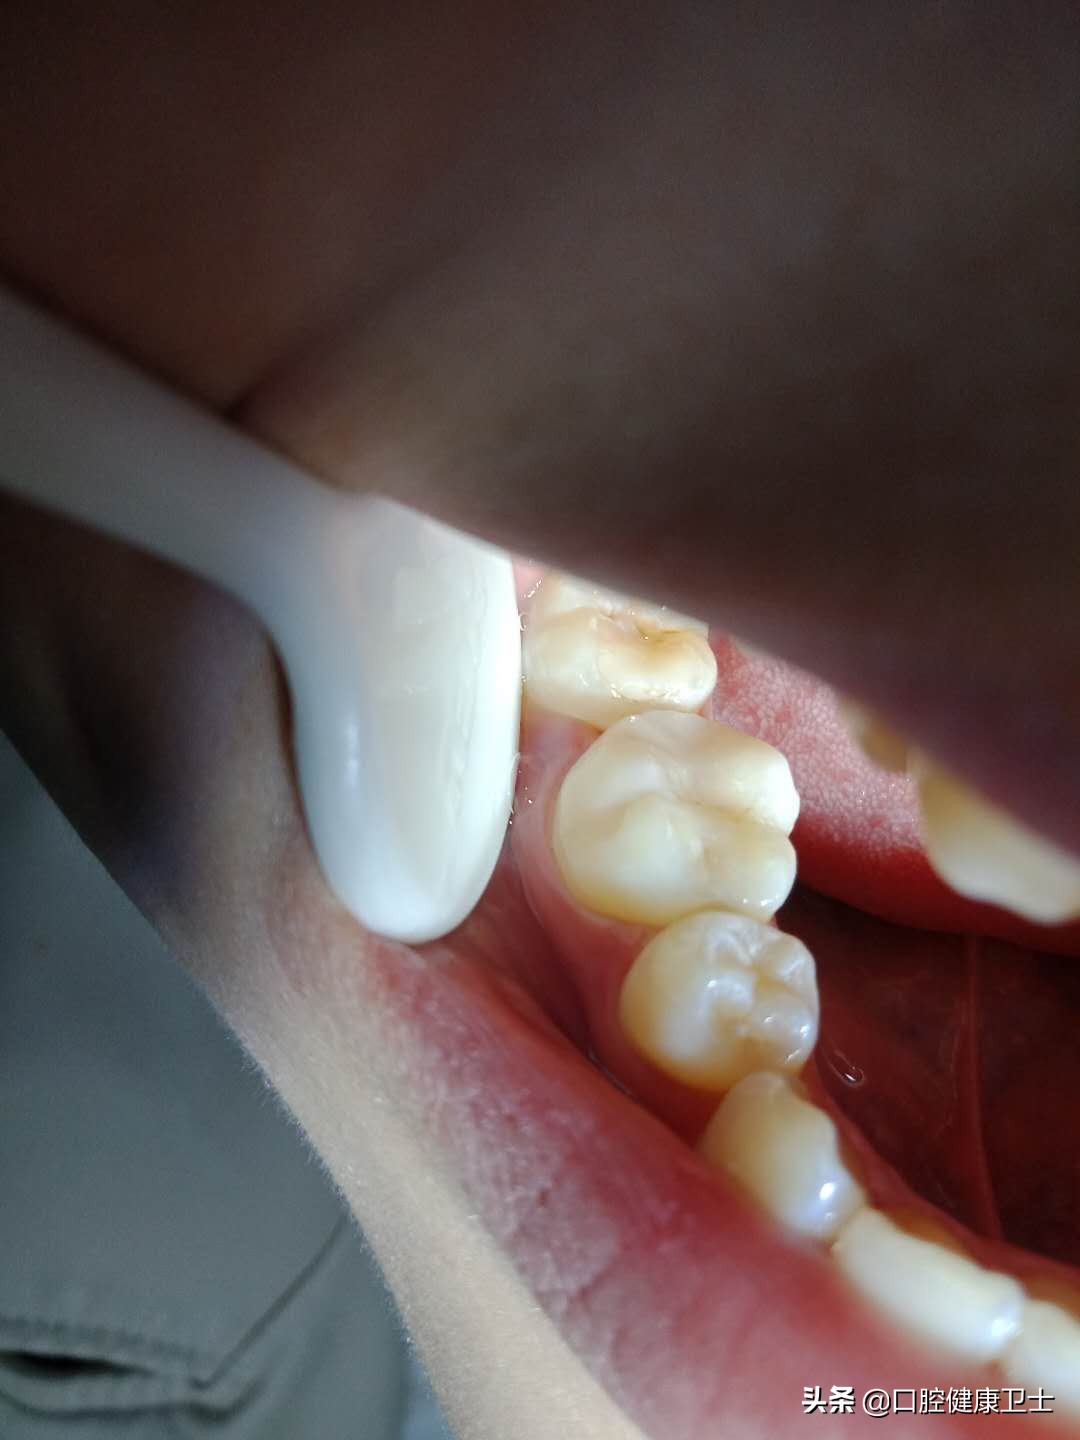

医生:你看,还有问题呢。看着两张图片,把材料去掉后,牙洞内的腐质都没有去除干净,这是不应该的,以后会出现继发龋,严重的会发展为牙髓炎和根尖周炎,引起剧烈疼痛。

患者:啊!这么黑啊,怎么这么脏。那您帮我清理干净再补吧。

医生:那是当然的,这是基本的要求,不仅要求去净腐质,还要制备洞型。